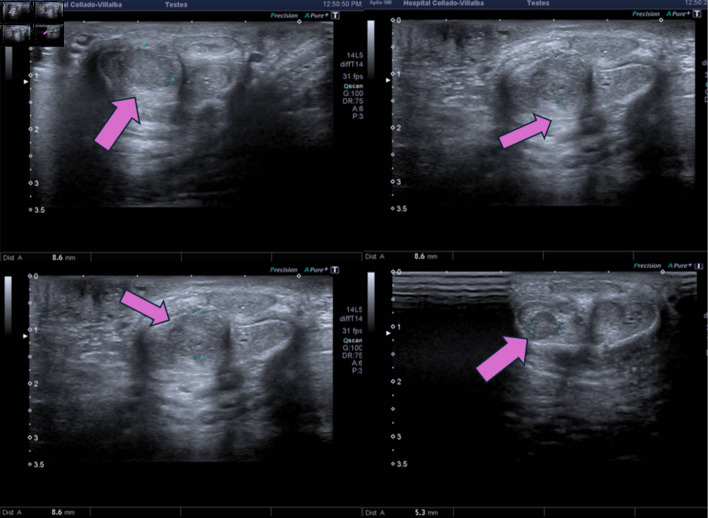

结直肠癌(CRC)向海绵体转移是一种非常罕见的疾病,通常与全身传播和预后不良有关。它常与肝脏和淋巴结累及同时出现。男性,43岁,会阴疼痛,直肠出血,尿路梗阻症状。影像学检查显示kras突变的直肠腺癌,分类为IV期,同步转移到海绵体和肝脏。治疗开始时采用FOLFOXIRI(亚叶酸、5-氟尿嘧啶、奥沙利铂和伊立替康)化疗,但由于肿瘤溶解综合征和与UGT1A1突变相关的毒性而停止。尽管改良FOLFOX(亚叶酸、氟尿嘧啶、奥沙利铂)加贝伐单抗,但病情进展迅速,促使患者转向姑息治疗,随后死亡。海绵体累及CRC反映疾病进展,经常伴有同步转移和有限的预期寿命。该病例强调了此类转移的不良预后意义,提示盆腔淋巴扩散可能是一种机制,并强调了药物遗传学对治疗耐受性和结果的关键影响。文献回顾强调了这种表现的侵略性生物学。结直肠癌的阴茎转移是罕见的,但具有破坏性,表明疾病是播散性的。多学科管理应优先考虑症状控制,并保留针对特定病例的靶向治疗。本病例说明有泌尿系统症状的恶性肿瘤病史的患者需要加强临床怀疑。

Metastasis to the cavernous bodies from colorectal cancer (CRC) is an exceptionally rare condition, typically associated with systemic dissemination and an ominous prognosis. It often presents synchronously with liver and lymph node involvement. A 43-year-old male presented with perineal pain, rectal bleeding, and urinary obstructive symptoms. Imaging studies revealed a KRAS-mutated rectal adenocarcinoma, classified as stage IV, with synchronous metastases to the cavernous bodies and liver. Treatment was initiated with FOLFOXIRI (folinic acid, 5-fluorouracil, oxaliplatin and irinotecan) chemotherapy but was discontinued due to tumor lysis syndrome and toxicity linked to a UGT1A1 mutation. Despite modified FOLFOX (folinic acid, fluorouracil, oxaliplatin) plus bevacizumab, the disease progressed rapidly, prompting transition to palliative care and subsequent death. Cavernous body involvement in CRC reflects advanced disease, frequently accompanied by synchronous metastases and a limited life expectancy. This case underscores the poor prognostic significance of such metastases, suggests pelvic lymphatic spread as a likely mechanism, and highlights the critical impact of pharmacogenetics on treatment tolerance and outcomes. A review of the literature emphasizes the aggressive biology of such presentations. Penile metastases from CRC are rare but devastating, indicating disseminated disease. Multidisciplinary management should prioritize symptom control, with targeted therapies reserved for select cases. This case illustrates the need for heightened clinical suspicion in patients with a history of malignancy presenting with urological symptoms.